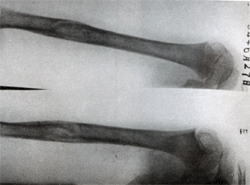

單房性骨囊腫診斷本症的診斷主要靠X線檢查和病理活檢。X線照片上顯示骨幹部中心性大透亮區有助於診斷。局部骨皮質變薄,體積略有膨脹。

X線檢查:囊腫一般位於長管狀骨的一端,局部骨幹的骨皮質略向外膨脹囊與骺板之間尚間隔有一小段松質骨。囊腫距骺板的遠近依病變發生時間的久暫和範圍而定。偶見囊腫穿透骺板進入骨骺如發生骨折,囊腫與骺板之間的松質骨可發生變形,但骨折多無移位